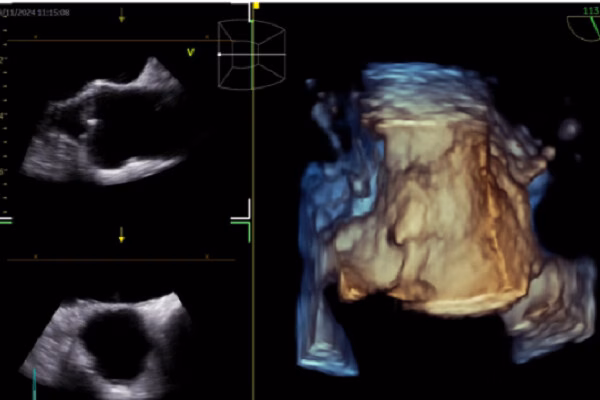

Trong siêu âm tim, AI đóng vai trò quan trọng trong việc nhận diện cấu trúc cơ tim, đo đạc tự động và hỗ trợ báo cáo và chẩn đoán. Công nghệ này không chỉ giúp giảm thiểu sai sót mà còn nâng cao tốc độ và hiệu quả trong quá trình chẩn đoán. AI cũng được sử dụng trong CT tim để cải thiện chất lượng hình ảnh, giảm liều xạ và cải thiện dự báo kết cục. Điều này đặc biệt quan trọng trong việc giảm thiểu rủi ro cho bệnh nhân.